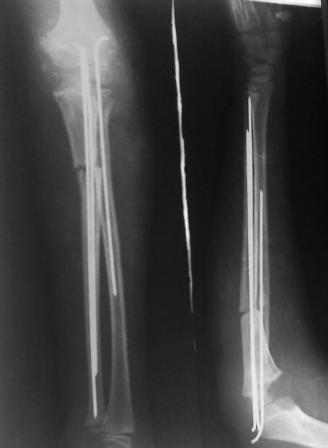

оперировали подобный случай около 6 мес назад. Отличие только в одном- давность травмы была до 2х лет. Использовали методику описанную в "Pediatric fractures and dislocations" Lutz von Laer, M.D.

Артротомия, иссечение рубцов, остатков кольцевидной связки. На проксимальный отдел локтевой кости стержневой аппарат (рекомендуют

Compact II выпущеный Stryker Howmedica, но за неименеем...), остеотомия проксимального отдела локтевой кости, вправление головки лучевой кости, замыкание аппарата, проверка стабильности головки

лучевой кости в движении, ушивание без пластики кольцевидной связки.

Данную методику применили впервые. После артролиза очевидная нестабильность головки луча. После остеотомии локтевой, вправления и

стабилизации аппарата головка луча при движениях на месте. Первые впечатления- "Либо чудо,либо фокус" (с) :))

1 подвывих головки лучевой кости в положении супинации - через 2 недели после операции- под ЭОП: аппарат разблокирован, повторное вправление головки, стабилизация аппарата.

2 По снятии аппарата через 2 мес после операции рефрактура в месте остеотомии(на фоне активного ротационного движения)- под контролем ЭОП выполнен

интрамедуллярный остеосинтез TEN. Положение головки луча стабильное.